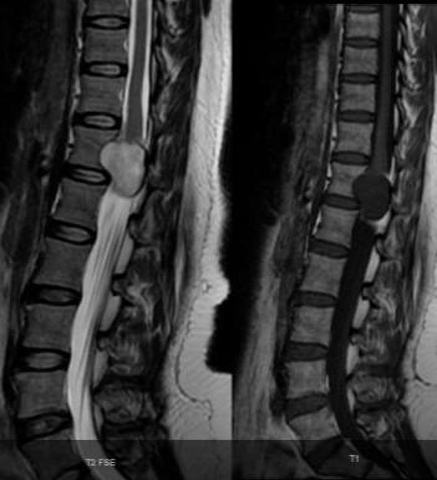

MRI:

- T1 - 75% are isointense

- T2 - more than 95% are hyperintense